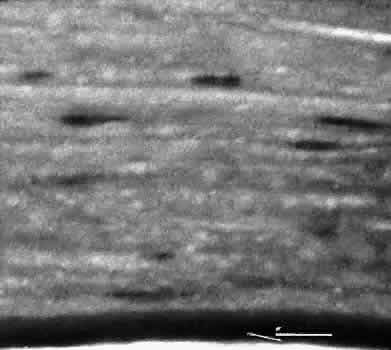

SCLERAL HEALING

The sclera itself does not participate directly in wound healing. Partial-thickness injuries are healed by formation of granulation tissue from the epi-scleral tissue in external wounds or from uveal tissue in internal wounds (Fig. 8). Full-thickness defects of the sclera heal by granulation tissue originating in the episcleral tissue and uveal tract. Mitomycin is used in filtering procedures specifically to prevent the formation of granulation tissue and promote establishment of an aqueous fistula.30